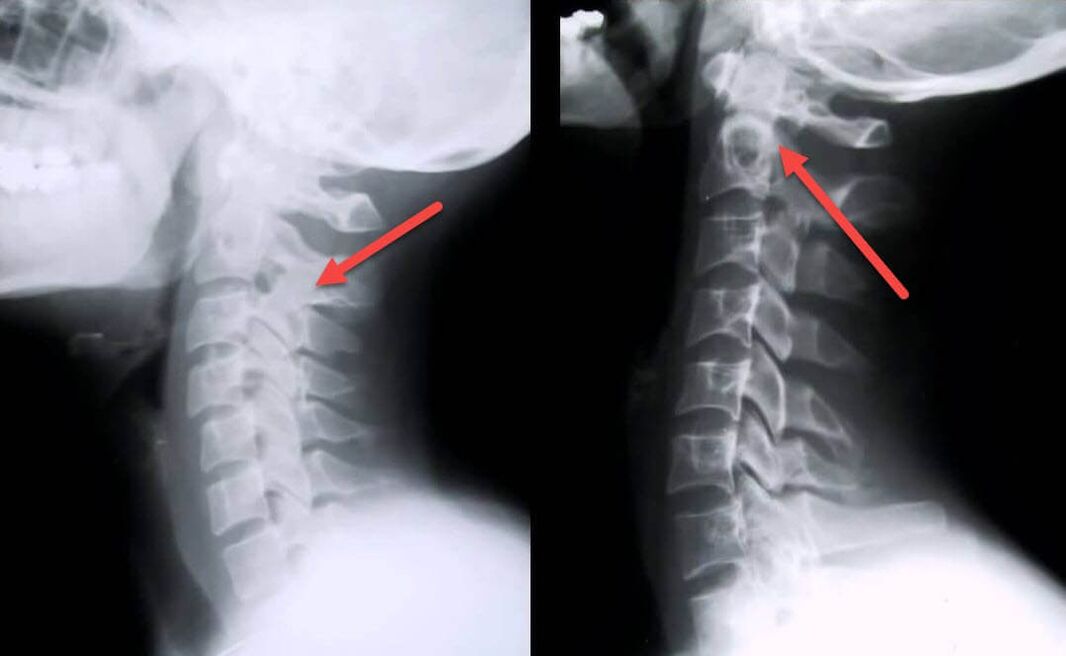

The most informative diagnostic procedure is radiography.Pathologies of the 1st degree correspond to the 1st or 2nd radiological stage.The resulting images visualize typical signs of illness.

| X-ray stages of cervical osteochondrosis of the 1st degree | Characteristic signs |

|---|---|

| Stage 1 | Minor changes in the curvature of the spine in the neck area, affecting one or more segments |

| Stage 2 | Slight thickening of the intervertebral discs, deformation of the uncinate processes, straightening of the lordosis, minor growths of the bone structures |